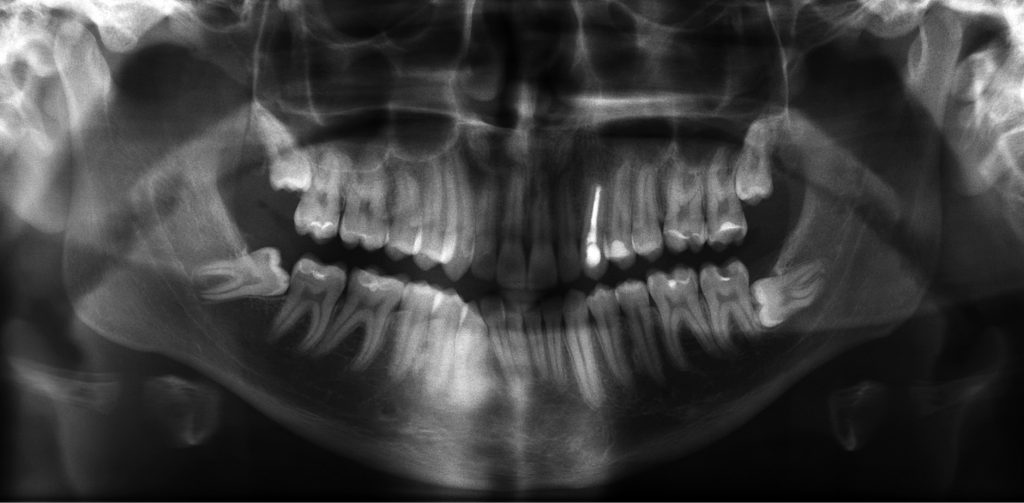

Streszczenie: W artykule przedstawiono opis leczenia zębiaka złożonego szczęki lewej, które przeprowadzono u 17-letniego mężczyzny. Ponieważ guz obejmował wierzchołek zęba 23, w pierwszym etapie przeprowadzono leczenie endodontyczne tego zęba, a następnie dokonano resekcji wierzchołka korzenia, jednocześnie wyłuszczając guz.

Summary: The treatment of complex odontoma of the left maxilla, which was conducted in 17-year-old man has been shown in this article. Because the tumor included an apex of the tooth 23 in the first stage endodontic treatment of the tooth was carried out and then in the single stage the root resection and enucleation of the tumor was performed.